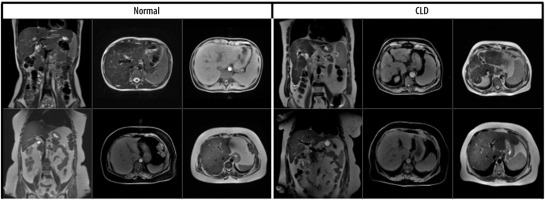

The dataset consisted of 1112 MRI slices from 184 patients, including both axial and coronal views. Specifically, 722 axial and 390 coronal images were included, and both imaging planes contained samples from normal and CLD classes. Images were input individually into the model, regardless of their orientation. No fusion method or explicit indication of image plane was used during training. This approach was chosen to evaluate the model’s ability to generalize across imaging planes and to reflect real-world variability in radiology practice. Examples of the dataset used are shown in Figure 1.

Figure 1

Coronal and axial images of normal/chronic liver disease (CLD) patients from the data set used